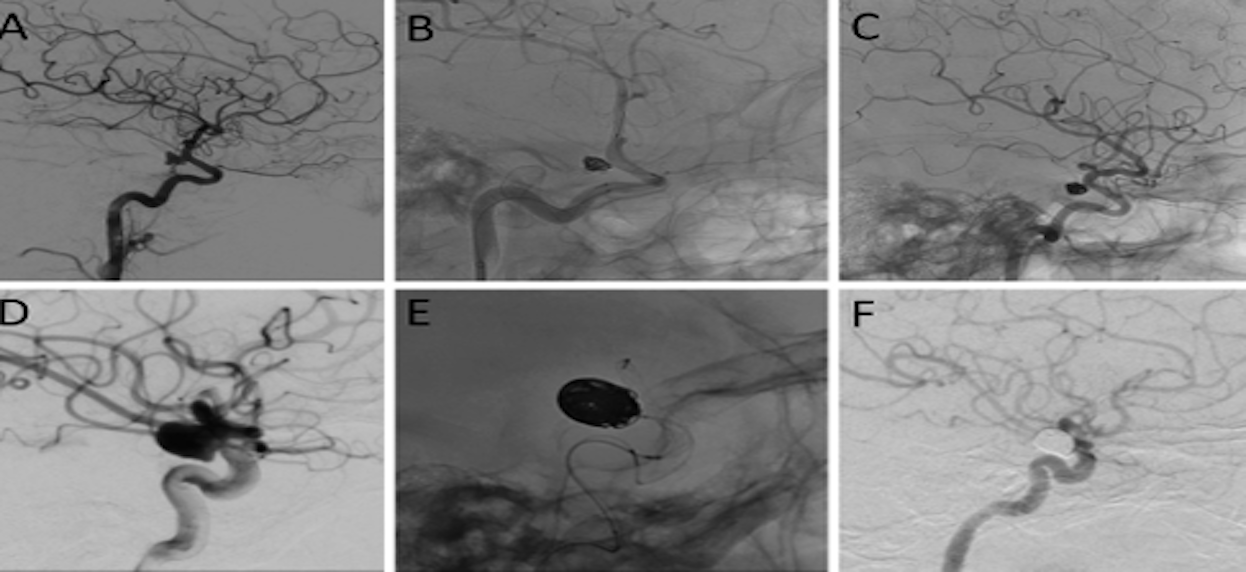

Y-Stent Technique Using Dual Comaneci Embolization Assist Devices for Coil Embolization of a Ruptured Wide-Necked Anterior Communicating Artery Aneurysm: A Technical Case Report

Kristine Ravina, Ira J Finch, Biraj Patel, Benjamin Yim

DOI: 10.1227/ons.0000000000001143 - 7/23